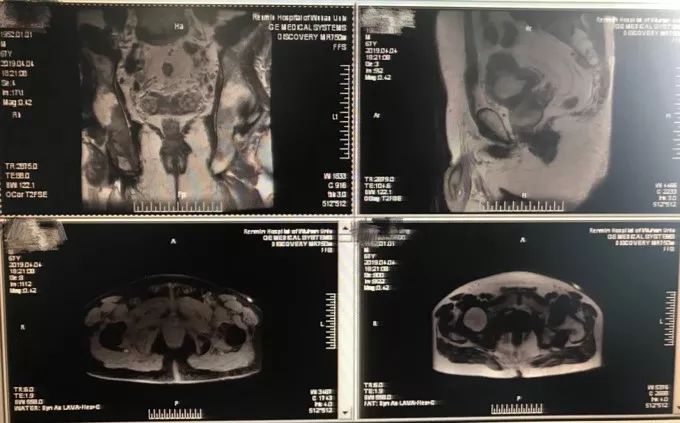

辅助检查影像表现:前列腺体积约64mm×41mm×46mm(左右径×前后径×上下径),T1WI示前列腺中央腺体区呈高等信号;T2WI示前列腺信号弥漫性均匀减低,外周带中部、右侧部见结片状更低信号灶,前列腺基底部包膜不完整,邻近脂肪间隙欠清晰;双侧精囊腺正常高信号消失;膀胱充盈欠佳,壁可见弥漫性增厚,增强扫描可见明显强化,腔内尿管可见。盆腔内未见明显积液。扫描范围所示左侧股骨头、右侧髂骨、双侧坐骨、耻骨见斑片状短T2长T1信号,增强扫描可见较均匀明显强化。

DWI示前列腺右侧外周带病灶、左侧股骨头、右侧髂骨及双侧耻骨可见弥漫受限,呈高信号。

前列腺外周带中部、右侧异常信号,考虑前列腺癌,伴双侧精囊腺、邻近膀胱壁受侵犯。

左侧股骨头、右侧髂骨及双侧坐骨、耻骨异常信号,考虑转移性病变。

图6 患者的影像学检查结果

(图片来源:湖北省人民医院泌尿外科廖文彪副教授的真实病例)